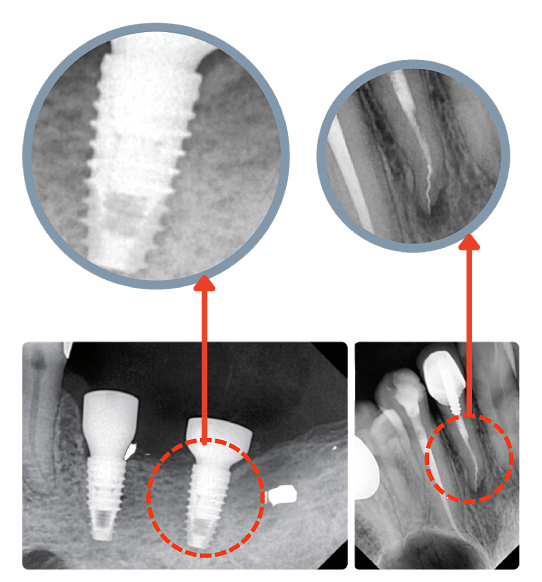

В комплекте с радиовизиографическим аппаратом EzSensor Classic Вы приобретаете 5 лицензий программного обеспечения EzDent-i со встроенным планировщиком имплантов

- Программное обеспечение EzDent-i ведет электронную картотеку с информацией о пациентах вместе с их изображениями

- Хранимые изображения доступны для просмотра и цифровой обработки фильтрами с любого компьютера в локальной сети

- Делает Вашу консультацию пациента более эффективной и наглядной с возможностью организации многооконного интерфейса для отображения информации, например, до и после лечения